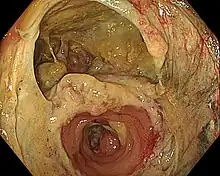

- Gastrointestinal (GI) tract: Esophagus, stomach, small bowel, large bowel, rectum, bile ducts, and pancreas. Virtually all elective resections of gastrointestinal organs are followed by anastomoses to restore continuity; pancreaticoduodenectomy is considered a massive operation, in part, because it requires three separate anastomoses (stomach, biliary tract and pancreas to small bowel). Bypass operations on the GI tract, once rarely performed, are the cornerstone of bariatric surgery. The widespread use of mechanical suturing devices (linear and circular staplers) changed the face of gastrointestinal surgery. A suture-free method for anastomosis of the colon to colon or rectum has been developed.[1][2]